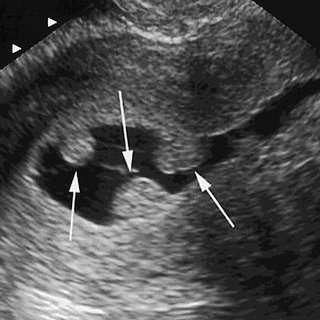

Realização de ecocardiograma fetal e pediátrico para um diagnóstico preciso e seguro do coração.

O que é o Ecocardiograma Fetal e quando devo fazê-lo?

É um ultrassom que avalia o coração do bebê ainda no útero. Idealmente, recomendo que ele seja feito entre a 24ª e 28ª semana de gestação — mas pode ser solicitado antes ou depois, conforme cada caso.